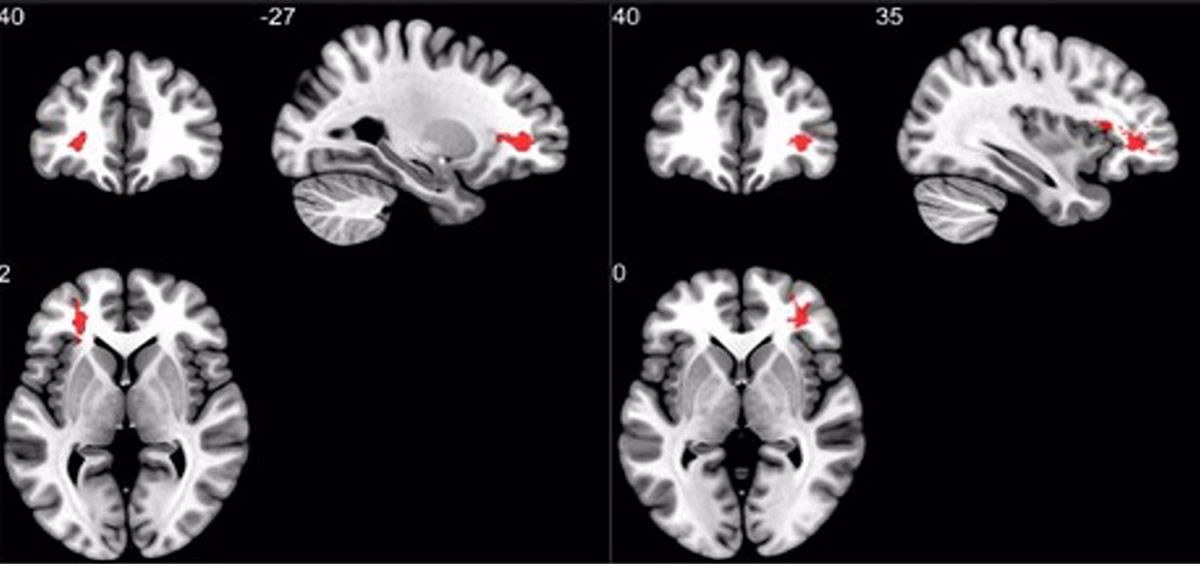

Para este estudio, los investigadores utilizaron imágenes ponderadas por susceptibilidad para analizar los efectos que la COVID-19 tiene en el cerebro. La susceptibilidad magnética indica en qué medida ciertos materiales se magnetizan en un campo magnético aplicado. "Nuestro estudio pone de relieve este nuevo aspecto de los efectos neurológicos de la COVID-19 e informa de anormalidades en los supervivientes de la COVID-19", ha comentado la coautora del trabajo Sapna S. Mishra.

Los resultados de la resonancia magnética mostraron que los pacientes que se recuperaron de la COVID-19 tenían valores de susceptibilidad más altos en el lóbulo frontal y el tronco cerebral en comparación con los controles sanos. Los investigadores también encontraron una diferencia en la región del diencéfalo ventral derecho del tronco cerebral. Esta región está asociada a muchas funciones corporales cruciales, como la coordinación con el sistema endocrino.